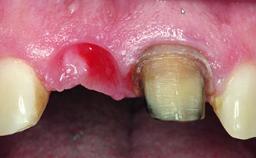

Replacement of a Compromised Upper Right Central Incisor: Hard- and Soft-tissue Augmentation, Late Placement of an RC Bone Level Implant

A 36-year-old male patient with a compromised maxillary central incisor was referred by his general dentist for consultation. The patient’s chief complaints were the gradual debonding of a temporary crown on the right central incisor and unsatisfactory esthetics due to an increasing diastema between the right central and lateral incisors. The patient reported a traumatic event some years previously, when a crown had been placed after root-canal treatment. The referring dentist wanted to provide a new crown restoration, but was concerned about the condition of the residual root. Anamnesis was negative for any other dental or periodontal pathology in the remaining dentition. The patient reported taking no medications: He was a smoker (10 to 15 cigs/day) and had realistic esthetic expectations.

Abutment Type CAD/CAM

Prosthesis Type FDP

Provisional Implant-Supported Prosthesis Prosthodontic margin > 3 mm apical to mucosal margin Prosthodontic margin > 3 mm apical to mucosal margin